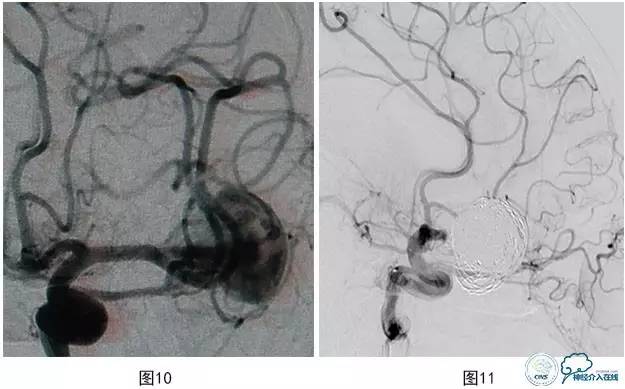

病例3:患者男,27岁。头痛2个月,左大脑中动脉M2段上干起始部靠近分叉部位巨大动脉瘤,下干起始部靠近瘤颈(图10),行支架辅助栓塞治疗,保护下干。术中载瘤动脉闭塞(图11),弹簧圈突入支架内(图12)。

图10 左MCA M2段上干起始部靠近分叉部位巨大动脉瘤

图11 载瘤动脉闭塞